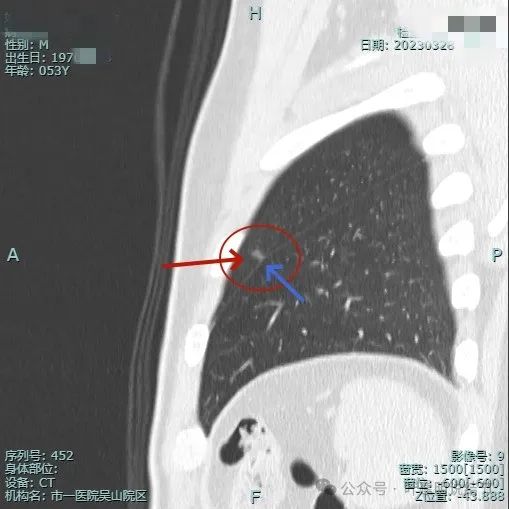

2023年3月影像展示:

病灶出现,密度淡,靠叶间裂较近,整体轮廓较为清楚。

密度纯,但不是太均匀,感觉稍不均,瘤肺边界清,贴胸膜近。

与叶间裂也是贴着的。

靶重建后见病灶密度不是很淡,轮廓较清,离叶间裂近但未见明显牵拉。

上图层面病灶贴着叶间裂,轮廓与瘤肺边界清楚,表面不光滑。

上图显得瘤肺边界稍模糊。

病灶似有极微细血管进入,贴着叶间胸膜但没有牵拉或明显凹陷。